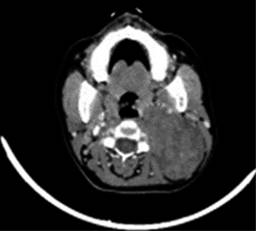

Sin datos de síndrome de respuesta inflamatoria sistémica, inestabilidad hemodinámica o compromiso cardiopulmonar, como complemento diagnóstico se solicita tomografía computarizada, la cual reporta gran masa redondeada de aspecto sólido de bordes regulares, bien delimitados, heterogénea de predominio hipodensa, con pequeñas zonas de menor densidad en su interior, sin identificar calcificaciones, con una densidad entre 24 y 37 UH y que posterior a la administración de medio de contraste intravenoso presenta una densidad entre 33 y 87 UH, localizado en nivel parafaríngeo izquierdo de 6.6 × 7.5 × 9.2 cm, lesión de espacio parafaríngeo izquierdo con sospecha de quiste branquial versus adenoma pleomorfo versus quiste branquial hemorrágico (Figuras 2 a 4).

Figura 2: Estudio de tomografía computarizada corte coronal con gran masa de aspecto sólido a nivel parafaríngeo izquierdo.

Figura 3: Tomografía computarizada corte axial con masa de apariencia sólida en espacio parafaríngeo izquierdo.

Figura 4: Tomografía computarizada corte sagital con lesión sólida en región cervical de aproximadamente 10 × 9 cm.